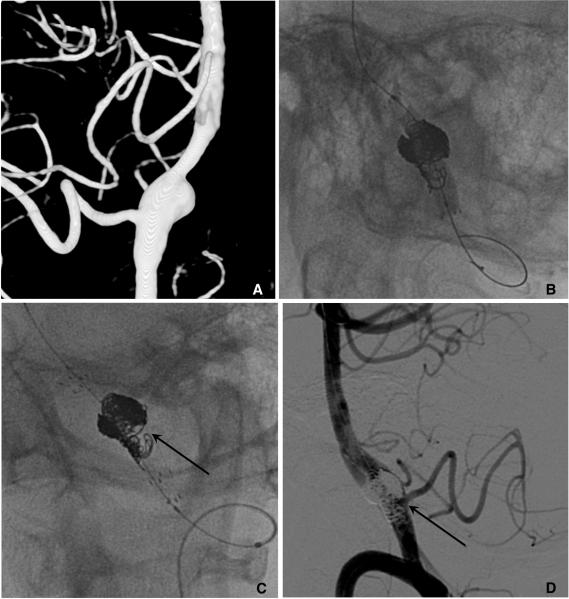

Stent application for the treatment of cerebral aneurysms.

Rapid and striking development in both the techniques and devices make it possible to treat most of cerebral aneurysms endovascularly. Stent has become one of the most important tools in treating difficult aneurysms not feasible for simple coiling. The physical features, the dimensions, and the functional characteristics of the stents show considerable differences. There are also several strategies and tips to treat difficult aneurysms by using stent and coiling. Nevertheless, they require much experience in clinical practice as well as knowledge of the stents to treat cerebral aneurysms safely and effectively. In this report, a brief review of properties of the currently available stents and strategies of their application is presented.

技术和设备的迅速显著发展使得大多数脑动脉瘤能够通过血管内治疗。支架已成为治疗难以单纯栓塞的复杂动脉瘤的最重要工具之一。不同支架的物理特性、尺寸和功能特点存在显著差异。使用支架辅助栓塞治疗复杂动脉瘤也有多种策略和技巧。然而,要安全有效地治疗脑动脉瘤,在临床实践中需要大量经验以及对支架的了解。本报告简要综述了目前可用支架的特性及其应用策略。